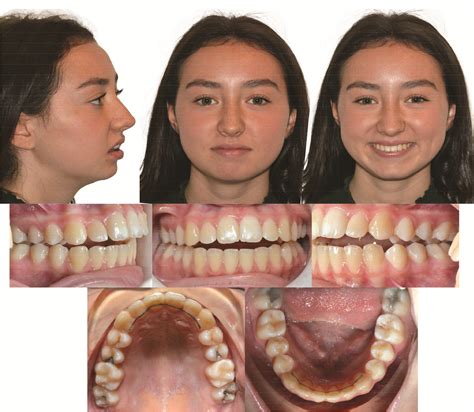

The progression of ICR can lead to significant changes in a person’s bite and facial profile. As the condyle shrinks, the lower jaw (mandible) shifts backward and upward, often resulting in an anterior open bite, where the front teeth no longer meet even when the back teeth are touching. This change can occur rapidly or slowly, often causing distress to patients who notice their smile or facial structure shifting unexpectedly.

• Facial asymmetry: A receding chin or a chin that appears to be drifting to one side.